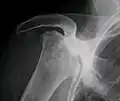

X-ray images of avascular necrosis in the early stages usually appear normal. In later stages it appears relatively more radio-opaque due to the nearby living bone becoming resorbed secondary to reactive hyperemia.[2] The necrotic bone itself does not show increased radiographic opacity, as dead bone cannot undergo bone resorption which is carried out by living osteoclasts.[2] Late radiographic signs also include a radiolucency area following the collapse of subchondral bone (crescent sign) and ringed regions of radiodensity resulting from saponification and calcification of marrow fat following medullary infarcts.

-

Radiography of total avascular necrosis of right humeral head. Woman of 81 years with diabetes of long evolution. -

Radiography of avascular necrosis of left femoral head. Man of 45 years with AIDS. -

Nuclear magnetic resonance of avascular necrosis of left femoral head. Man of 45 years with AIDS. -

The intravertebral vacuum cleft sign (at white arrow) is a sign of avascular necrosis. Avascular necrosis of a vertebral body after a vertebral compression fracture is called Kümmel's disease.[20] -

Pathology of avascular necrosis, with a photograph of a cross-section of the involved bone at top left. The reactive zone shows irregular trebaculae with empty lacunae, and fibrosis of the marrow space.